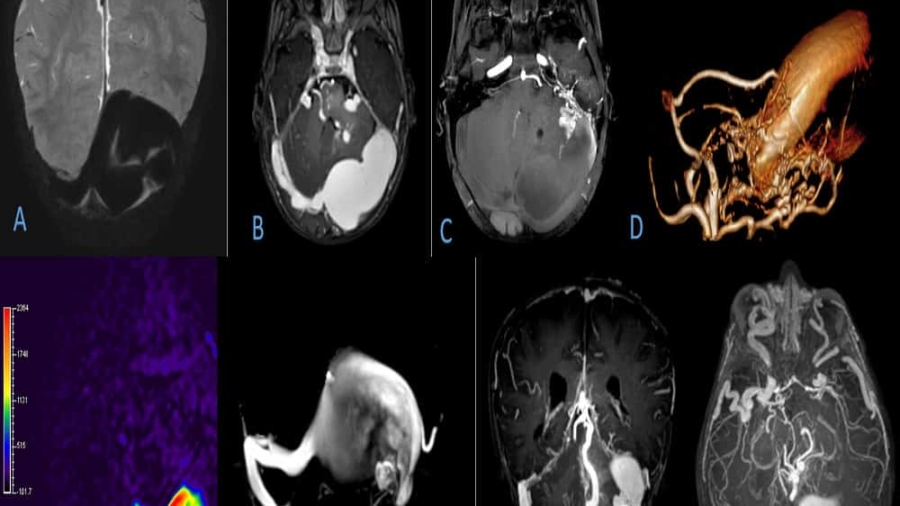

11 year old female child presented with history of right sided hearing loss, vertigo and imbalance since 6 months, right facial numbness, facial asymmetry and difficulty swallowing since 3 months, headache and vomiting since 1 month duration.